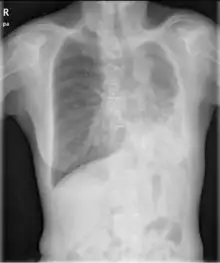

- Chest X-ray is effective in detecting the traits of lung herniation.[1] The unaffected side of lung tends to undergo hypertrophy, and move towards the empty space in the chest wall on the opposite side.[1] This herniation could be indicated by fluoroscopy.[1] With age increasing, the herniation progresses and ease its detection.[1]

- Electrocardiogram is useful in detecting dextrocardia, a possible outcome when agenesis is present on the right lung.[1] With empty space in the chest wall, the heart rotates in clockwise direction, shifting the location for apex beat occurrence.[1] Hence cardiac physical examination also helps as heart sounds is heard best at right chest with dextrocardia.[1][4] In the condition of left side agenesis, heart sounds will appear to be louder than normal.[1][4]

- CT scan, bronchoscopy, bronchography and Magnetic resonance imaging also contributes to the observation of patients’ lung anatomy.[4]